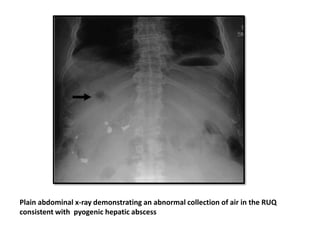

Plain abdominal x-ray demonstrating an abnormal collection of air in the RUQ

consistent with pyogenic hepatic abscess

Plain abdominal x-raydemonstrating an abnormal collection of air in the RUQ consistent with pyogenic hepatic abscess